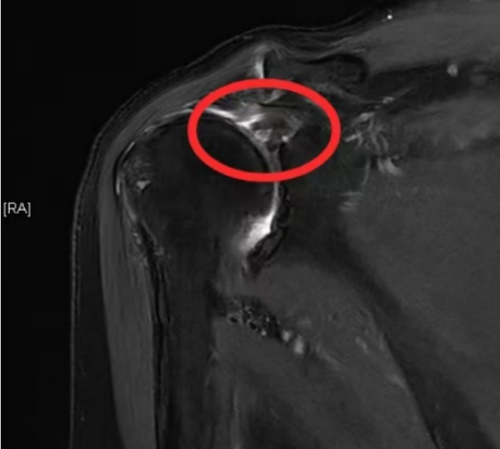

核磁检查发现右肩肩袖损伤